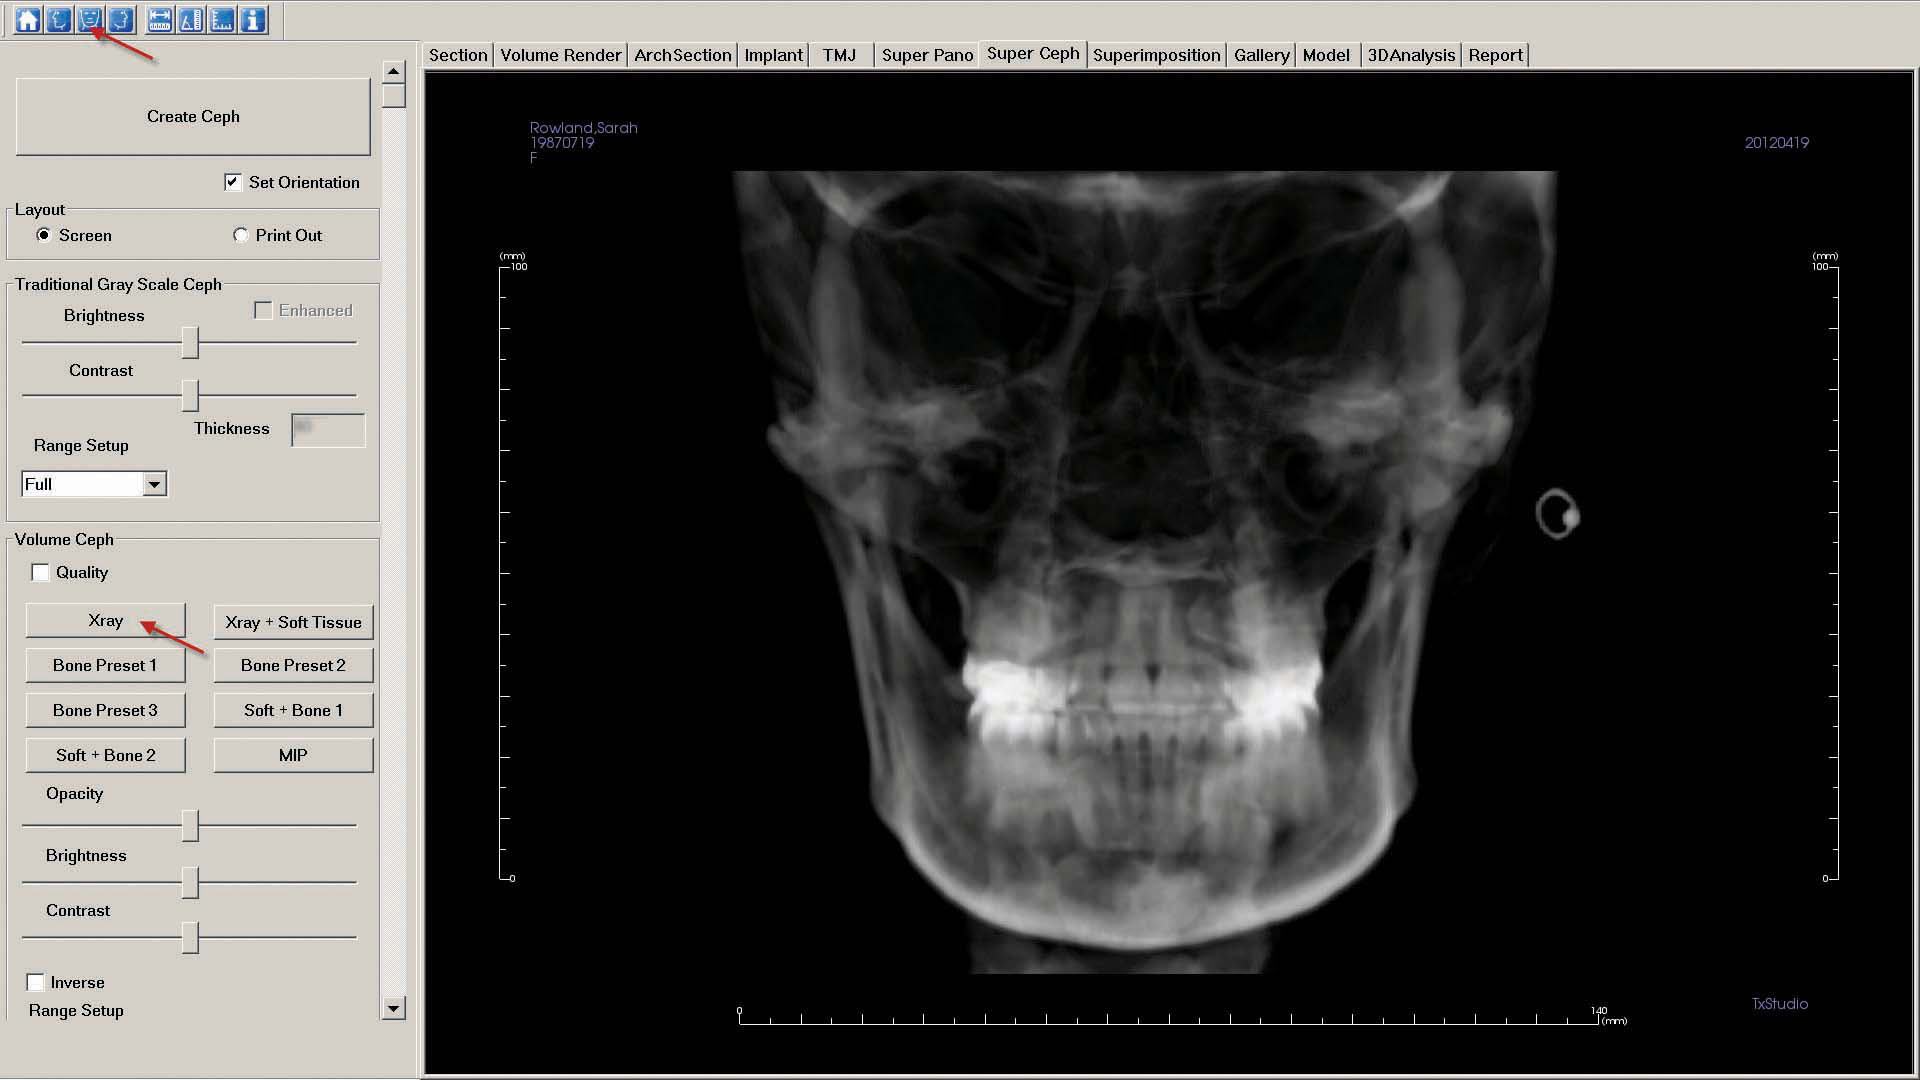

b. Click the "Super Ceph" tab to create the "Frontal" image. Select the "Front View" icon in the upper left corner, and click "X-ray."

As described in step 7, "Capture to Gallery" and name the image "Frontal."